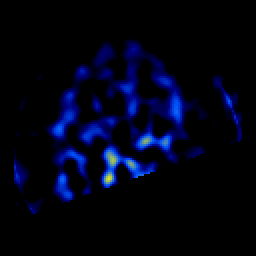

SPECT TL Study #4 -- Slice #44

[Home][Help][Clinical][Tour 1][Tour 2][Tour 3] Slice 44